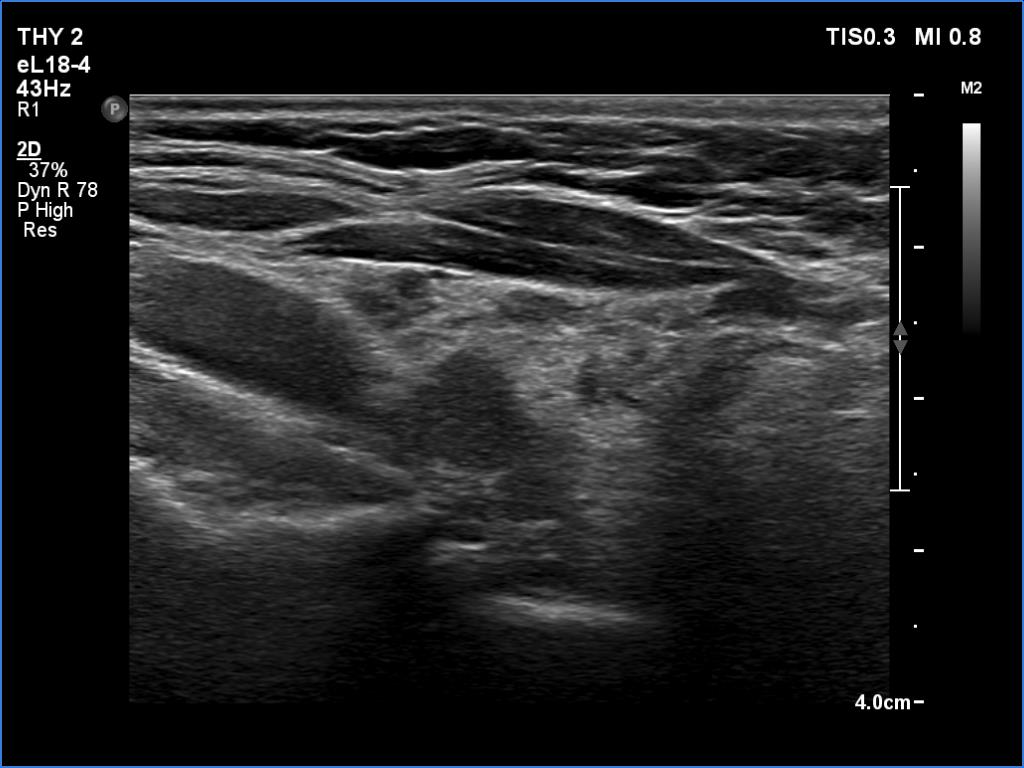

Ultrasonography. The thyroid was decreased in size and presented numerous discrete hypoechoic lesions which presented with irregular borders. These discrete areas corresponded to more active foci of thyroiditis.